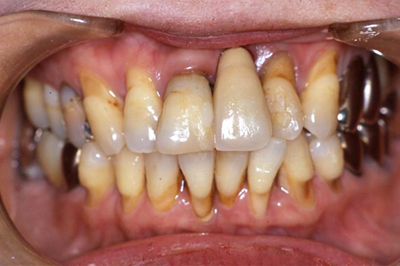

インプラント施術例

歯を削りたくない、入れ歯をどうしても入れたくないという時、インプラント治療を行っています。

施術前

施術後